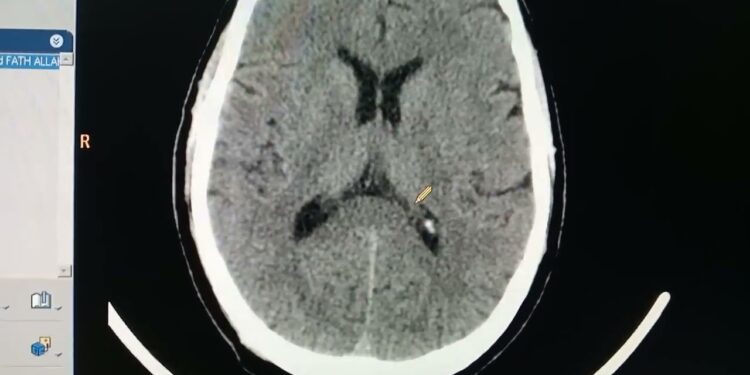

أوضح وزير الصحة والسكان أن الأشعة لها دور محوري في التشخيص الدقيق والتخطيط الفعّال للعلاج، مشيراً إلى أهمية تعزيز برامج التعليم الطبي المستمر لفنيي الأشعة واستخدام أجهزة المحاكاة في التدريب العملي.

وأضاف أن المؤتمر يسهم في رفع مستوى الكفاءات العلمية والتدريبية للعاملين في هذا المجال، مؤكداً على أن الابتكارات التقنية في الأشعة تُعد جزءاً أساسياً في تحسين النتائج الصحية للمرضى.